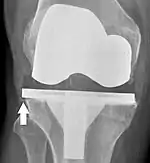

Loosening of the prosthesis can be indicated on X-ray by thin radiolucent spaces around the implant, or more obviously by implant displacement.[55]

Knee replacement is routinely evaluated by X-ray, including the following measures:

- FFC: frontal femoral component angle. It is typically regarded as optimal when being 2–7° in valgus.[62]

- FTC: frontal tibial component angle, which is regarded as optimal when being at a right angle. A varus position of more than 3° has generally been found to increase the failure rate of the prosthesis.[62]

- Anterior femoral notching (the femoral component causing reduced thickness of the distal femur anteriorly), seems to cause an increased risk of fractures when exceeding about 3 mm.[63]

- LTC: lateral (or sagittal) tibial component angle, which is ideally positioned so that the tibia is 0–7° flexed compared to at a right angle with the tibial plate.[62]